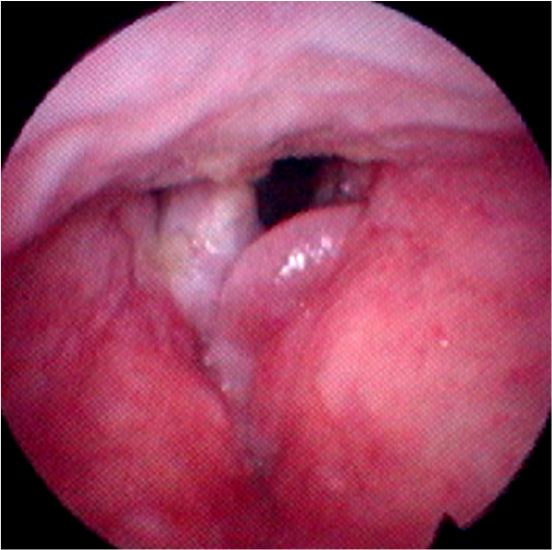

・声帯ポリープは声帯結節、声帯ポリープ、ポリープ様声帯の3種類にわけられます。

・ポリープ様声帯は、両側の声帯が全体的にむくんで生じる ことが多く、ひどい声がれになります(ダミ声)。症状が進むと呼吸困難を起こすこともあります。タバコが原因になる場合もあります。

ポリープ様声帯